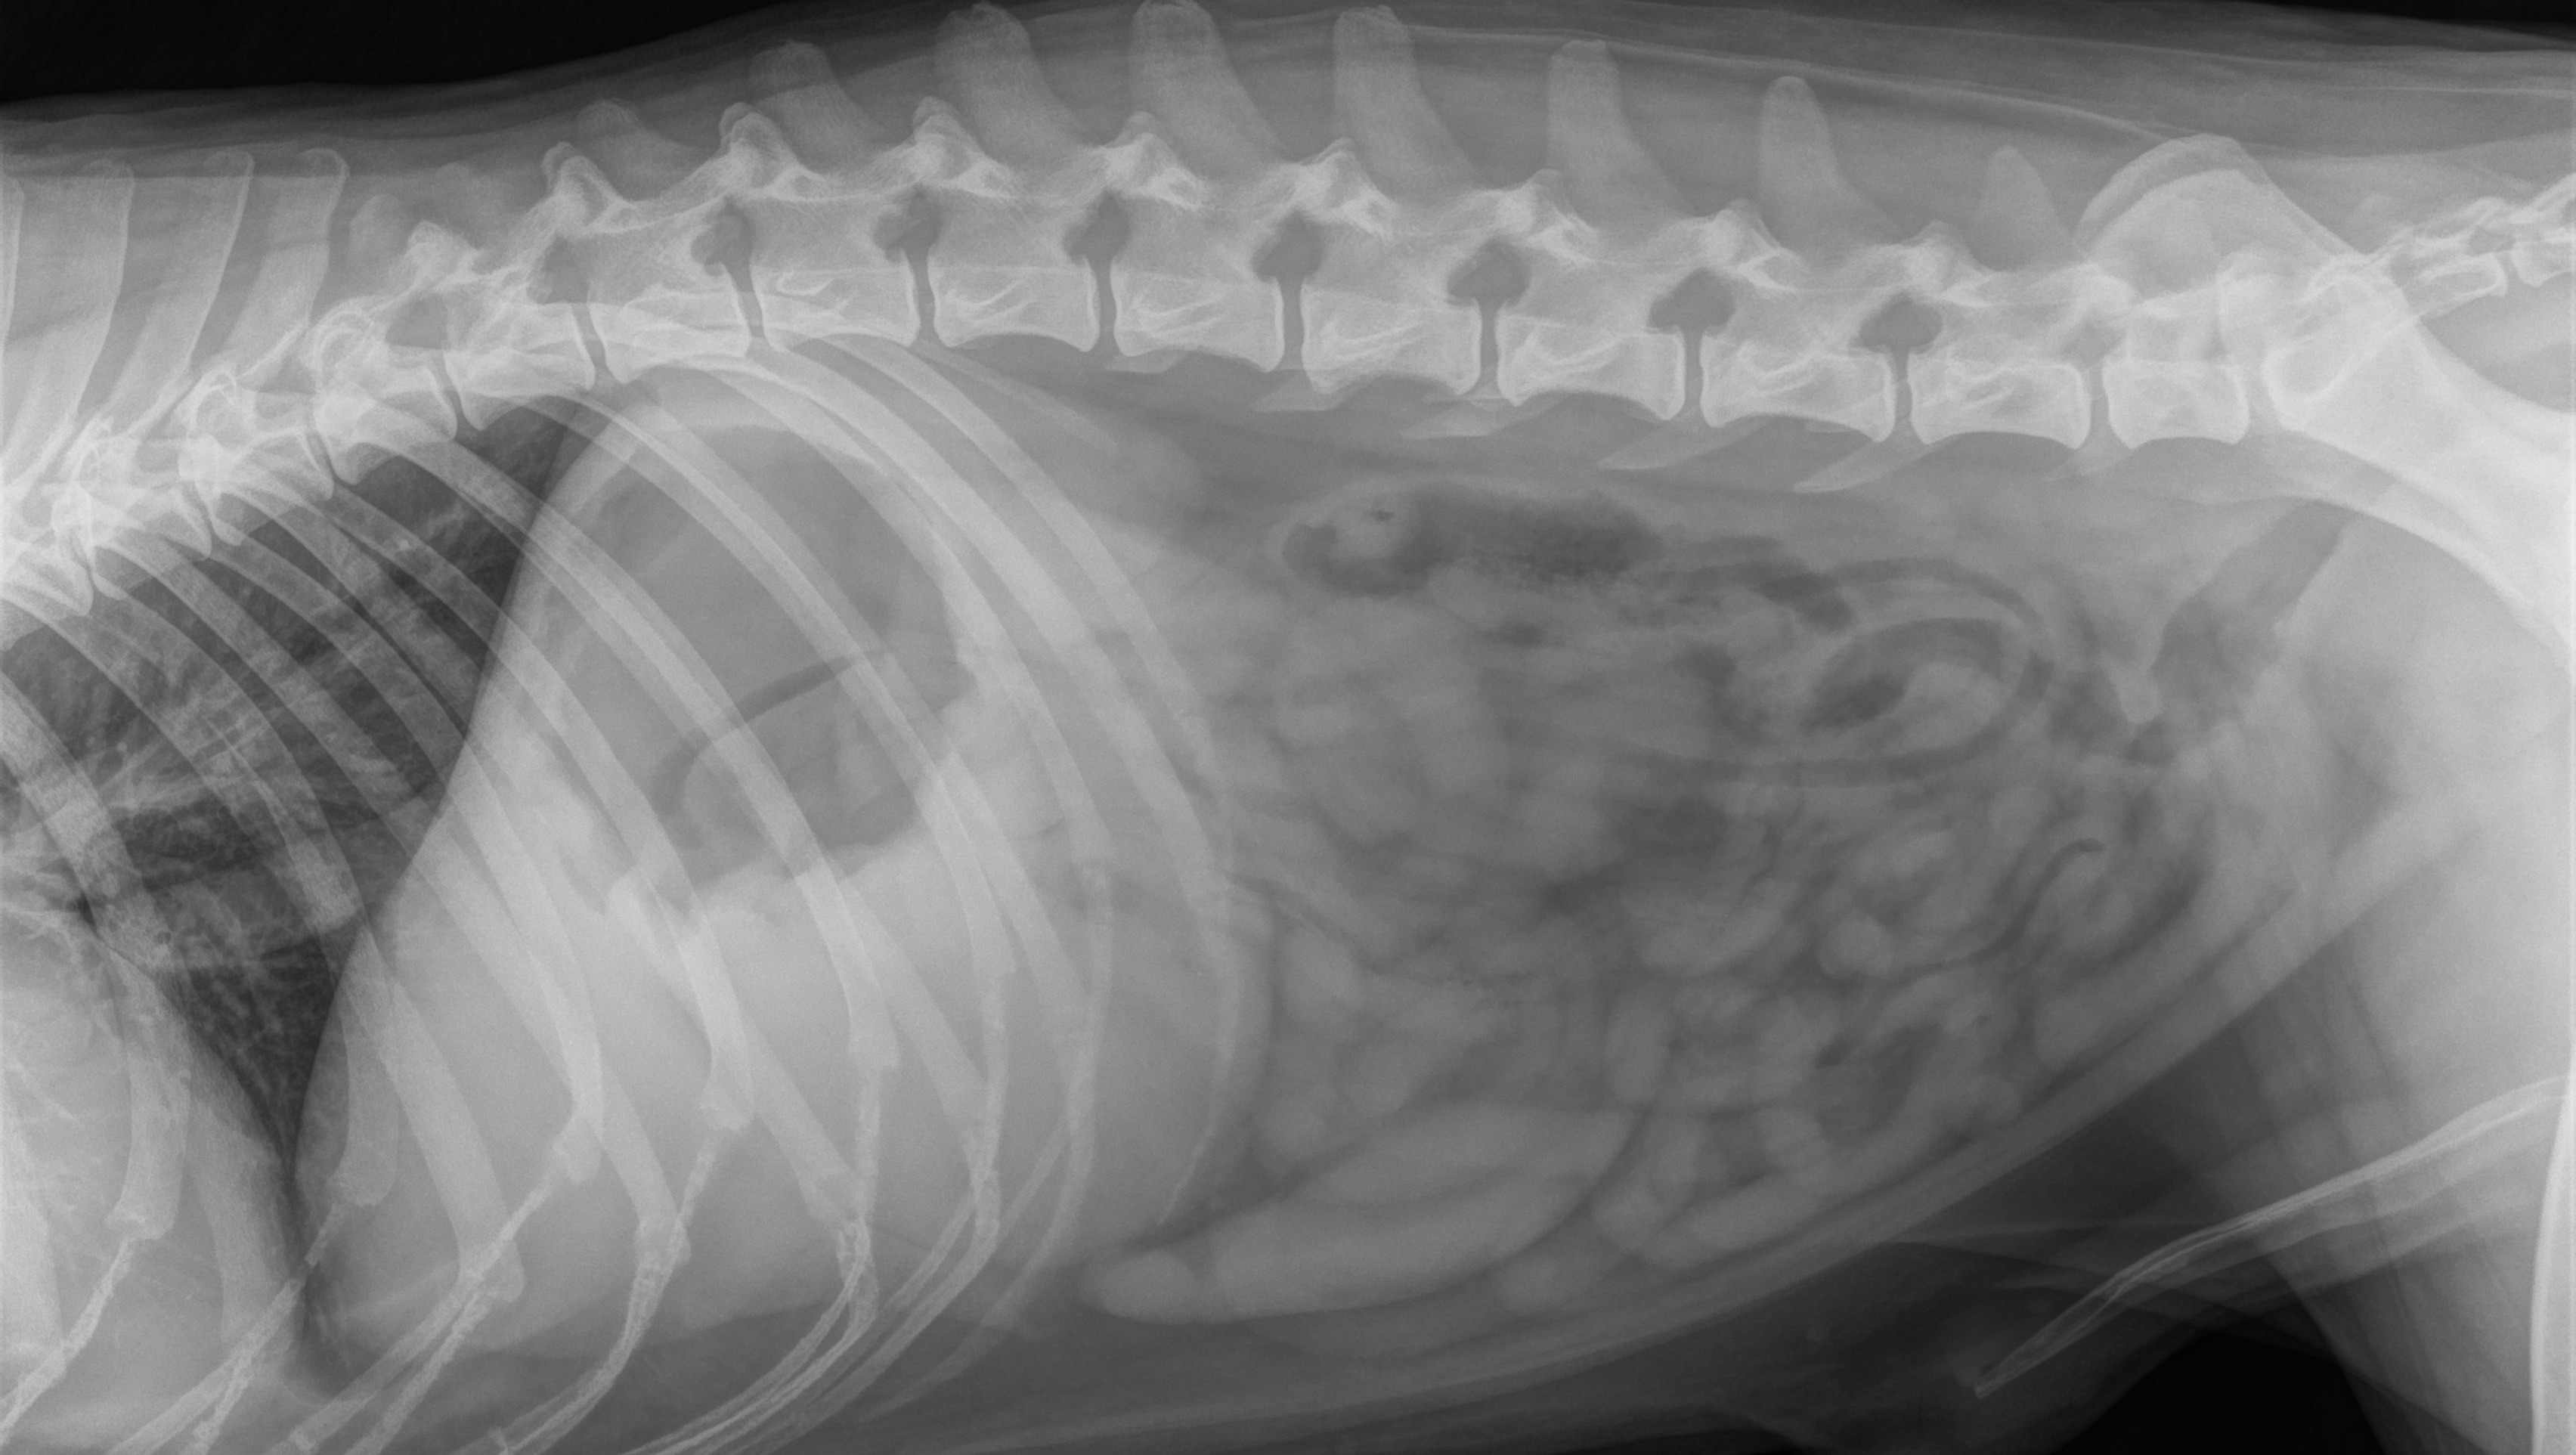

Last night, my sweet dog Kito was diagnosed with stomach /liver cancer … and our world turned upside down. What we thought was a minor health issue turned into devastating news after an emergency vet visit.

Kito's X ray suspecting Mass in his liver or stomach....